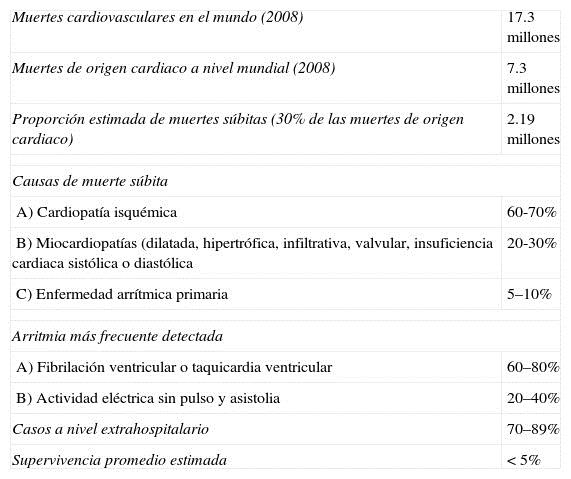

La muerte súbita es un problema de salud público a nivel mundial5,8,6. Se reporta en diferentes poblaciones y continúa representando al menos del 20-30% de los decesos de origen cardiaco; en países como EE. UU. es la responsable del 7-18% de los decesos totales5. En México no conocemos la incidencia y prevalencia de la muerte súbita o del paro cardiaco súbito. En Francia la incidencia es de 32.1 casos por millón de habitantes/año10, en China es de 41.3 casos por 100,000 habitantes/año11, en EE. UU. la incidencia varía y va de 70 a 155 casos por 100,000 habitantes/año, lo que puede representar entre 185,000 y 400,000 casos anuales5,12. En la población infantil se ha informado una incidencia de 3.2 casos por 100,000 habitantes/año en Holanda13. El mayor número de casos se presenta en población entre 45 a 75 años de edad, debido principalmente al desarrollo de enfermedad arterial coronaria12,14-16. En algunas poblaciones como las de origen latino, en New York, se ha observado que al menos el 45% de los casos son menores de 65 años de edad6,12. Tiene un franco predominio en la población masculina, pero con una participación cada vez mayor en el sexo femenino donde se ha informado que puede representar el 35% de la mortalidad de origen cardiaco17,18. En México no conocemos la incidencia y prevalencia, pero podemos hacer un cálculo aproximado de las víctimas de muerte súbita; en el 2008 se reportaron 59,579 fallecimientos en adultos por cardiopatía isquémica19, es probable que al menos 30% de estos fueran de forma súbita, lo que representa 17,873 casos/año. Dos trabajos publicados en nuestro país estiman que el número puede ser tan alto como de 70,000casos/año20,21. A nivel mundial, en el 2008 ocurrieron 17.3 millones de muertes por enfermedades cardiovasculares, de las cuales 7.3 millones fueron por cardiopatía isquémica22; es probable que el 30% de estos fallecimientos fueran de forma súbita, lo 2 que representa 2.19 millones de muertes súbita/año. La Tabla 1 muestra un resumen de la información estadística aproximada del paro cardiaco súbito a nivel mundial.